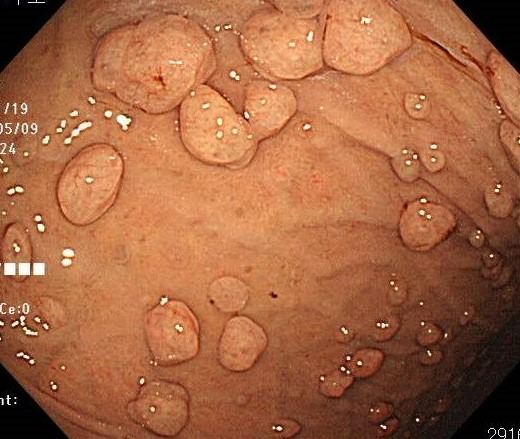

*典型的な胃底腺ポリープ

胃底腺ポリープとは、胃の上部に位置する「胃底部」と呼ばれる部分に生じる、小さく丸い隆起性の病変です。

大きさは数ミリ程度のことが多く、表面はなめらかで艶があり、胃カメラで観察すると半透明の丸い粒のように見えるのが特徴です。

このタイプのポリープは、中高年の女性に比較的多く、また胃酸を抑える薬(プロトンポンプ阻害薬:PPI)を長期間服用している方にもよく見られます。

多くの場合、胃底腺ポリープは良性であり、がん化のリスクは極めて低いとされています。

ピロリ菌に感染していない「ピロリ菌陰性」の人に多くみられるのも特徴で、ピロリ菌感染によって生じる他のタイプのポリープとは発生メカニズムが異なります。

治療が必要となることはほとんどなく、基本的には経過観察で問題ありません。